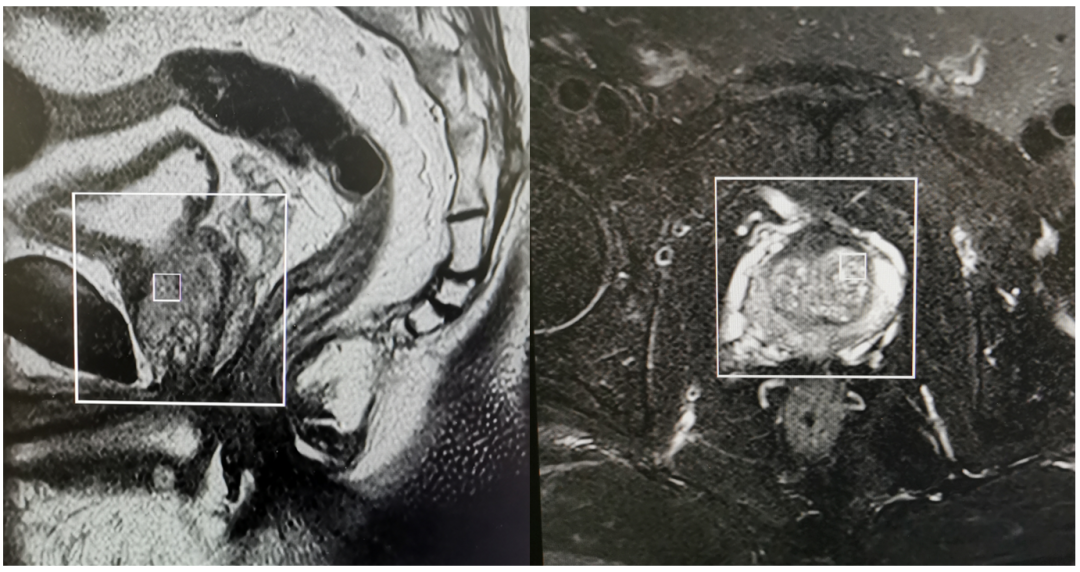

前列腺MR(平扫+增强+波谱)(2024-9-9)

2.png

前列腺体积增大,其前后径、左右径及上下径分别约35mm*45mm*38mm,T2W1显示前列腺中央带及移行带均匀性增大,移行带前缘见结节状DWI高信号,ADC低信号,直径约0.8cm,边界欠清晰,矢状位及冠状位显示前列腺向上部分突入膀胱,呈双弧形压迹,波谱分析前列腺局部见倒置峰改变。考虑前列腺Ca可能性大,PI-RADS 4分,建议临床必要时穿刺检查。